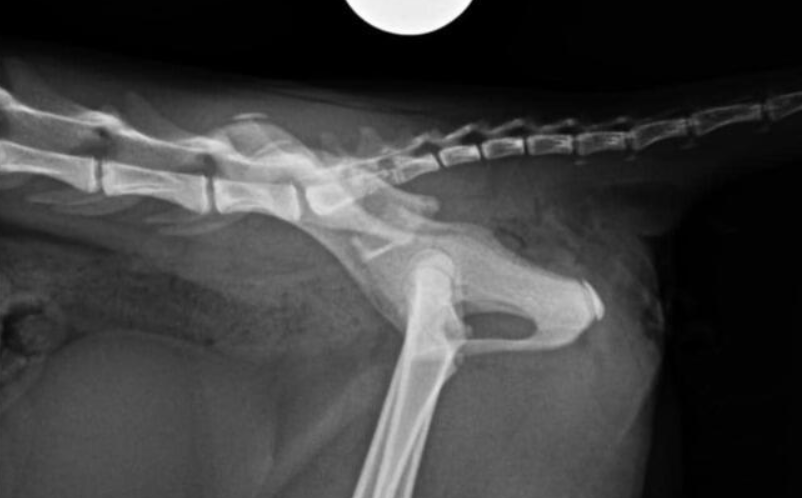

Kotka została znaleziona pod blokiem przez cudowną osobę, która nie pozostała obojętna i natychmiast powiadomiła odpowiednie służby! W wyniku upadku Felcia odniosła bardzo poważne obrażenia: przesunięcie kręgów w odcinku krzyżowym kręgosłupa, złamanie miednicy i zwichnięcie stawu biodrowego. Na szczęście zachowała czucie, więc mamy wielką nadzieję na powrót małej do pełnej sprawności, do czego długa droga...

Kicia jest już pod opieką naszej fundacji! Jest już po skomplikowanej operacji, której podjął się znakomity ortopeda, doktor Kacper Weigel. Z całego serca dziękujemy Panu doktorowi oraz całemu zespołowi Kliniki Weterynaryjnej Puławska za błyskawiczną pomoc i zaangażowanie! Wszystko się udało i po 6 tygodniowym unieruchomieniu w kennelu rozpoczniemy rehabilitację.